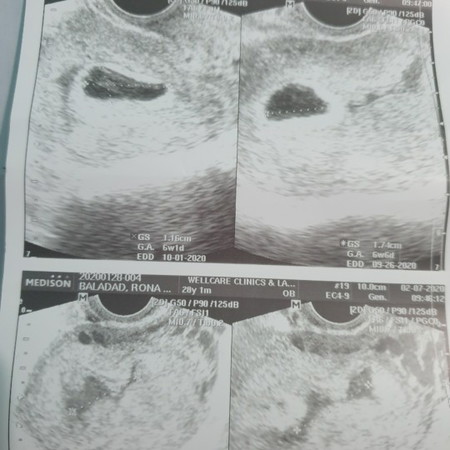

Anembryonic Pregnancy / blighted ovum

My hubby and I were grieving. We just loss our baby at 7 weeks. Done with D&C procedure. I want to share this story about blighted ovum. Pregnancy test thru urine and blood can detect your pregnancy. However only transvaginal ultrasound can detect this blighted ovum. Meron syang Sac pero wala syang laman. I have subchroinic hemmorhage from 1cc to 3.5cc. It means may internal bleeding ako. I dont have spotting or bleeding. Its my 2nd day after the operation at konti lang ang bleeding ko after raspahin. My doctor advised me na magD&C or dilation and curettage procedure kasi pwede maging lason ang sac at tumaas ang infection ko sa blood. For those moms who are complaining about the results of the gender. Here we are grieving all we wanted is a healthy baby regardless of any gender. And for those na otw na.. kaya nyo yan always ask your OB and stop self medicating. I have to sign this off.